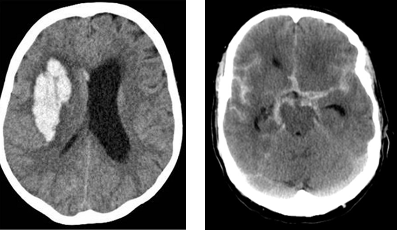

Which type of haemorrhagic stroke are the following CTs?

Whats the difference between Intracerebral haemorrhage vs Subarachnoid haemorrhage (SAH)?

Which causes a thunderclap headache?

Intracerebral haemorrhage is bleeding into the brain parenchyma: basal ganglia particularly effected

SAH is bleeding into the subarachnoid space. thunderclap headache